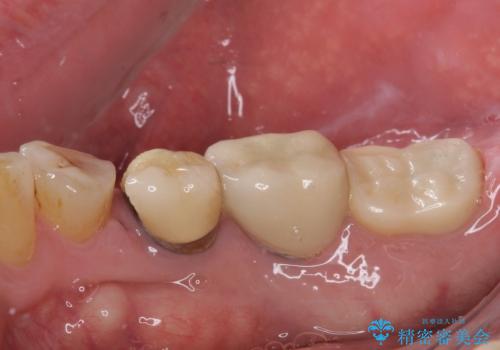

- 強い咬合力により表面のセラミックが剥がれ、裏打ちの金属が見えてしまっていることを気にして来院された患者様です。

仮歯に変えた後、咬合力に耐えることを目的に強化セラミッククラウンにて補綴することとしました。